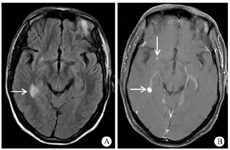

入院初步诊断:"艾滋病合并播散性结核病(累及中枢神经系统、呼吸系统以及淋巴系统),暴露型TB-IRIS"。3月15日予异烟肼(0.9 g/d)、利福平(0.6 g/d)、乙胺丁醇(1.0 g/d)、吡嗪酰胺(1.5 g/d)、莫西沙星(0.4 g/d),以及阿米卡星(0.4 g/d)强化抗结核治疗,拉米夫定(0.3 g/d)、替诺福韦(0.3 g/d)和依非韦伦(0.6 g/d)抗-HIV治疗,复方磺胺甲噁唑(0.48 g/d)预防肺孢子菌肺炎治疗,静脉滴注地塞米松(5 mg/次,1次/d)抗炎以及多处浅表淋巴结切开引流治疗。患者病情未见明显改善,反复高热,精神极度萎靡,食欲差。4月5日突发气胸,需要双侧胸腔闭式引流;破溃淋巴结难以愈合,大量脓液分泌;腹胀、腹痛难以忍受(严重时需要使用地佐辛止痛治疗)。因患者病情危重,4月6日遂加用复方磺胺甲噁唑(1.44 g/次,4次/d)联合卡泊芬净(第1天70 mg,第2天开始50 mg/d,1次/d,静脉滴注)经验性抗肺孢子菌肺炎治疗,在此基础上予甲基泼尼松龙(40 mg/次,1次/12 h,静脉滴注;逐渐减量)联合沙利度胺(50 mg/次,3次/d)抗炎治疗。考虑到药物相互作用问题,停用利福平,改为利奈唑胺(0.6 g/次,1次/12 h,静脉滴注)抗结核治疗。ART方案调整为拉米夫定(0.3 g/d)、替诺福韦(0.3 g/d)和多替拉韦(50 mg/d)。4月18日查增强CT示广泛淋巴结脓肿:颈部、锁骨、双侧腋窝、肝门部、腹膜后、右侧盆壁内侧淋巴结肿大,中心坏死,环形强化;部分淋巴结融合成团,分界不清,右侧腰大肌脓肿形成。住院期间出现的主要不良反应为骨髓抑制(血常规中WBC最低1.4×109/L,Hb最低55 g/L)。经过综合治疗,患者病情缓慢改善,胸腔闭式引流维持时间约1个月拔除引流管。5月10复查胸部CT较前改善。6月13日查颅脑MRI右侧颞叶侧脑室旁结节有所增大(图3),考虑与免疫重建相关,因患者无明显中枢神经系统症状,继续巩固治疗1个月后出院。7月13日出院时患者抗结核方案调整为异烟肼(0.6 g/次,1次/d),乙胺丁醇(1.0 g/d),吡嗪酰胺(1.5 g/d),莫西沙星(0.4 g/d)以及利奈唑胺(0.6 g/次,2次/d),抗炎药物为甲泼尼松龙(12 mg/d,每2周减量1片)和沙利度胺(50 mg/次,3次/d;每2周减量1片)。8月20日随访颅脑磁共振示原病灶明显吸收。继续随访3个月,患者病情稳定,无不适主诉。

注:A.右侧脑室旁及基底节区小片状T2高信号(箭头示), B.增强后可见下结节样强化及环形强化(箭头示),周围水肿带未见强化